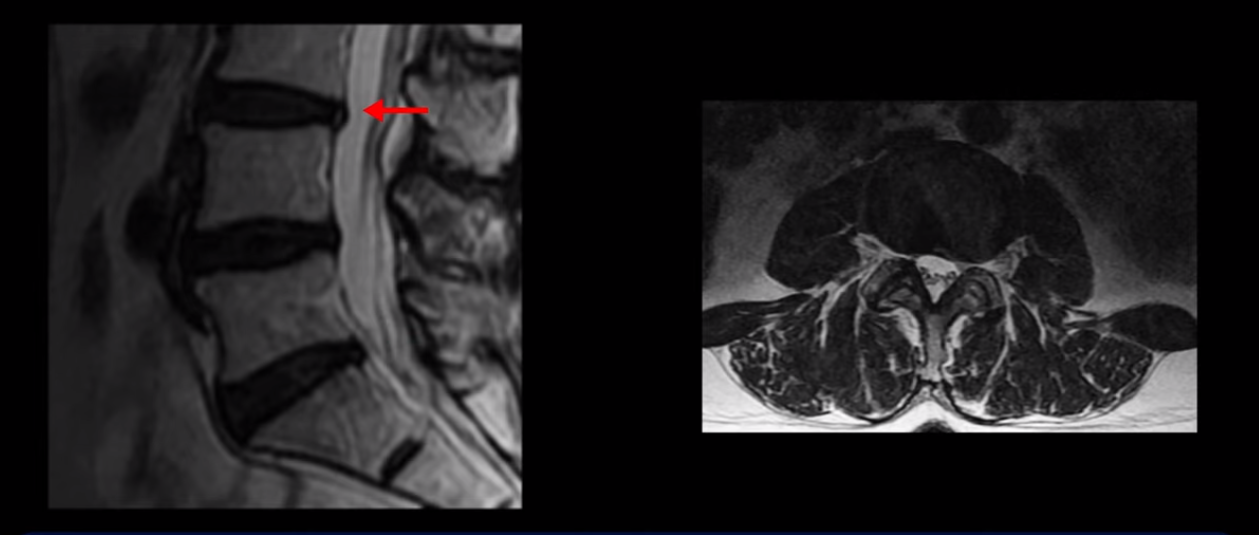

이분 MRI를 보시면 허리 세 마디가 퇴행은 있으나

척추관도 3번 4번

전부 다 충분히 넓고 왼쪽 다리 쪽으로 신경이 나가는 추간공도 전부 다 충분히 넓은 상태입니다.

신경이 눌려 보이지 않는 겁니다. 그러니까 수술 후 MRI를 보고 모든 병원이 전부 다 ‘수술은 잘돼 있다’, ‘아무것도 해줄 게 없다’ 그냥 기다리라고만 얘기했다고 합니다. 신경외과, 정형외과, 재활의학과가 서로 다른 과로 전과시키면서 다들 아무것도 해줄 게 없다고 하니 희망을 잃은 상태였다고 했습니다.